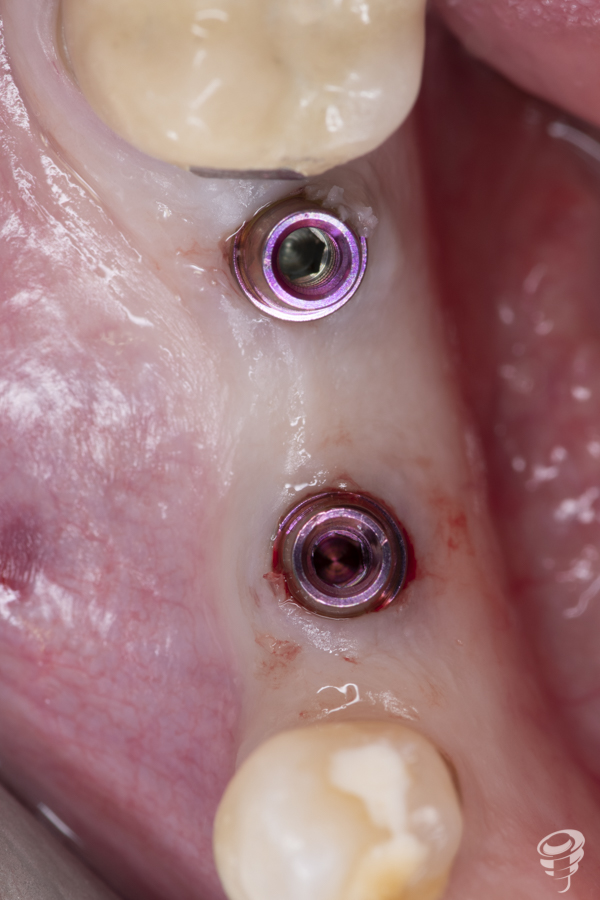

Una vez realizada la expansión ósea, se insertan los dos implantes Galimplant de 4 mm de diámetro y de 10mm de longitud (IPX 4010). Estos implantes son de titanio grado IV con conexión cónica a 11 grados. Una vez colocados los implantes, retiramos el porta implantes con un mosquito e insertamos 2 pilares multi-posición rectos estéticos altura 3mm (MUSR04030)

La colocación inmediata de estos pilares es fundamental para la obtención de resultados óptimos. No sólo es necesario que el implante se integre , sino que además es necesaria una relación optima entre la conexión del implante, el pilar protésico y un buen sellado biológico, la cual, en muchos casos, se ve alterada por la conexión y desconexión de diferentes pilares durante la fase de oseointegración y restauración del implante.

Cuando se coloca un implante se crean tres tipos de epitelio: oral, periimplantario y periimplantario del surco. La mucosa alrededor del implante crea un sellado muy parecido al diente natural; sin embargo, la anchura biológica se ve aumentada (3 a 4 mm aproximadamente). Las células epiteliales se unen a la superficie del titanio de forma similar a como se une el epitelio a la superficie del diente. El epitelio tiene una rápida proliferación, creciendo sobre la superficie de la fribina que se deposita de forma inmediata sobre el aditamento protésico; el cual, una vez contactado con el pilar protésico, se desplaza en sentido corono-apical, originando el epitelio de unión de unos 2 mm aproximadamente , uniéndose a la superficie mediante hemidesmosomas en los primeros días tras la cirugía.

Cuando colocamos un implante, los tejidos blandos que lo rodean crean una barrera en forma de primera fijación a la superficie del implante que bloquea la entrada de bacterias y toxinas orales en el espacio entre implante y tejidos biológicos, sellando la región.

La colocación del pilar protésico de forma inmediata en el mismo momento de la cirugía y sin desconexiones, mantiene íntegro el sellado biológico en todo el momento obteniendo mejores resultados. Además, el uso de un pilar multi-posición recto estético hace que la interfase diente-pilar quede más distante del punto de contacto implante-hueso. Ésto da como resultado el alejamiento del infiltrado inflamatorio del tejido conectivo de la cresta ósea marginal. Este cambio de plataforma mantiene el hueso distante de la plataforma del implante minimizando la pérdida ósea marginal periimplantaria.